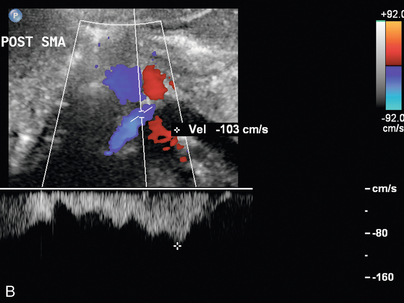

Синдром Щелкунчика

Феномен «щелкунчика» возникает в результате сдавления левой почечной вены между верхней брыжеечной артерией и аортой и может привести к гипертензии левой почечной вены, гематурии и образованию варикозно расширенных вен. Важно помнить, что у некоторых здоровых людей при КТ, МРТ или УЗИ можно обнаружить расширенную левую почечную вену. Следовательно, следует применять другие критерии, в том числе высокий коэффициент доплеровской скорости ( рис. 9-23 ) и высокий коэффициент диаметра вен, как описано в недавней литературе. Из-за сложности потенциального хирургического вмешательства может потребоваться измерение градиента давления между НПВ и левой почечной веной в качестве подтверждения до того, как будет диагностирована клинически значимая компрессия почечной вены. Визуализация крови из устья мочеточника при ретроградной уретероскопии также может быть полезной. Цветная допплерография может обеспечить неинвазивное подтверждение компрессии почечных вен с соотношением пиковых скоростей более 5:1, когда обнаружены коллатеральные вены. На КТ может наблюдаться резкое изменение калибра вен, когда вена пересекает СМА, обычно с «клювовидным» видом.

РИСУНОК 9-23 Щелкунчик с почечной веной. У пациента с необъяснимой гематурией спектральная допплерография преаортальной левой почечной вены (А) демонстрирует нормальный низкоскоростной поток, 8 см/с. (B) Когда вена пересекает аорту и SMA (допплеровские ворота), наблюдается видимое сужение с повышенной пиковой систолической скоростью, 103 см/с.